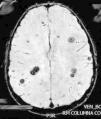

Caso clínicoNiño de 10 años, sin antecedentes y normal desarrollo psicomotor. Presenta empeoramiento del estreñimiento habitual, dolor abdominal e imposibilidad para la micción en las últimas 24h; con anestesia del pie derecho, aparición progresiva de parestesias en extremidad inferior derecha (EID) y dificultad progresiva para la deambulación. Exploración: debilidad y disminución del tono en EID. Hemograma y bioquímica sanguíneas con LDH, las radiografías abdominal y de columna lumbar, y la TAC abdómino-pélvica fueron normales. Con sospecha de mielopatía compresiva, y ante progresión de la debilidad en EID, con imposibilidad para la deambulación, se realiza RM medular, donde se aprecia lesión tumoral en T7 (fig. 1). Se inicia tratamiento con dexametasona intravenosa a dosis altas, progresando la debilidad a la otra extremidad, y se decide realizar cirugía descompresiva medular; previo a esta, la RM cráneo-medular muestra múltiples lesiones compatibles con cavernomas (fig. 2).

La lesión medular es resecada completamente, y su análisis confirma un cavernoma. Reanamnesiando, se nos refiere que en una TAC realizada a la madre 22 años antes, se le dijo que presentaba múltiples lesiones, sin poder precisar su naturaleza, permaneciendo asintomática.

La evolución fue satisfactoria, con recuperación progresiva de la función vesical, fuerza en EID y la deambulación autónoma. La RM cerebral materna confirmó la CM. El estudio genético en nuestro paciente, demostró una mutación en CCM1/KRIT1, en heterocigosis, c.418 C>T, que produce un cambio en la pauta de lectura que da lugar a la aparición de un codón STOP (p.Arg140*). No descrito previamente.